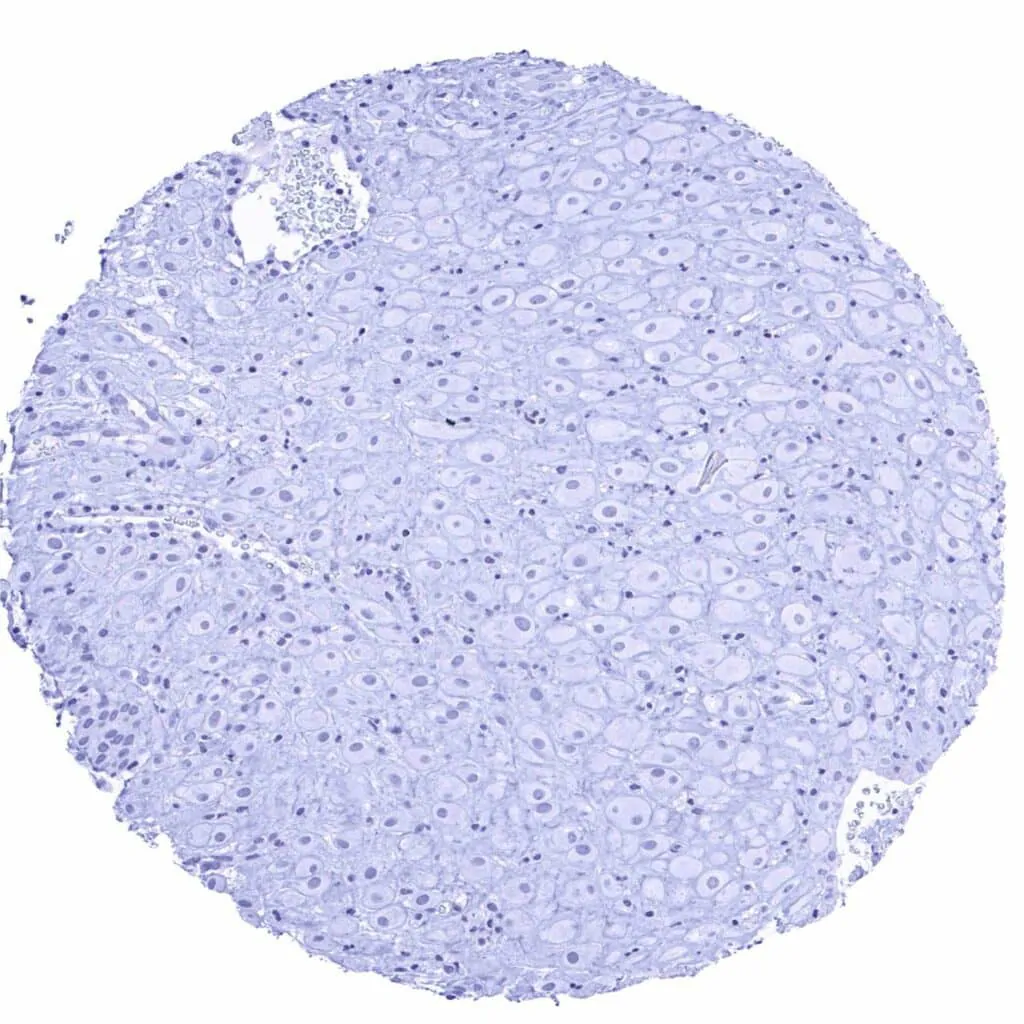

Prostate – Strong membranous CD38 staining of most epithelial cells. Staining is weaker or absent in basal cells